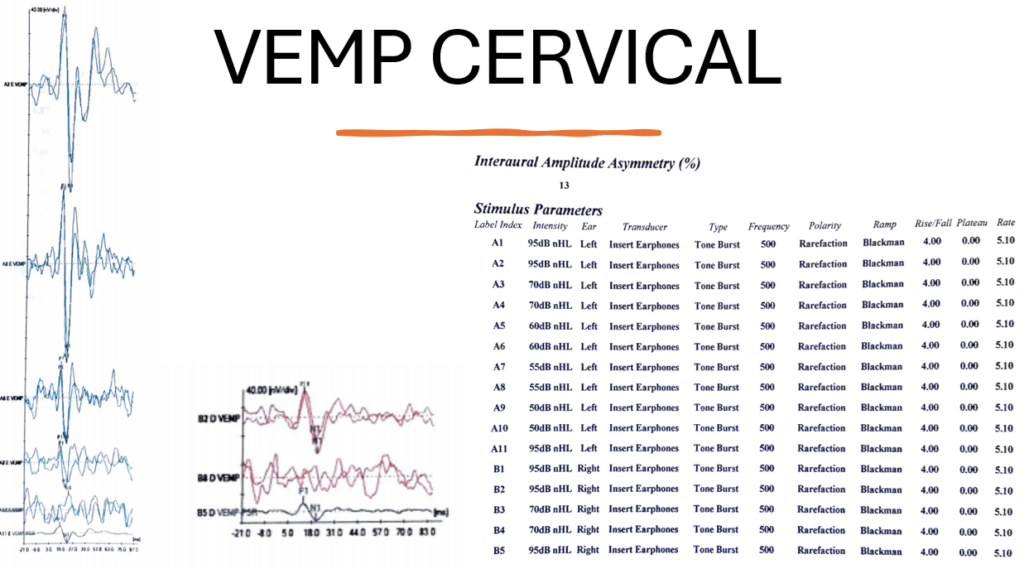

O exame do Vemp cervical mostra claramente que o potencial inibitório P1-N1 permanece presente mesmo com um limiar de estímulo rebaixado na orelha esquerda (Com 55dBnHL tivemos resposta = limiar na orelha esquerda). Isso não ocorreu na orelha direita. Portanto, pelo Vemp cervical, estamos diante de um caso de Síndrome da Terceira Janela Labiríntica acometendo a orelha esquerda (lado mais sintomático).